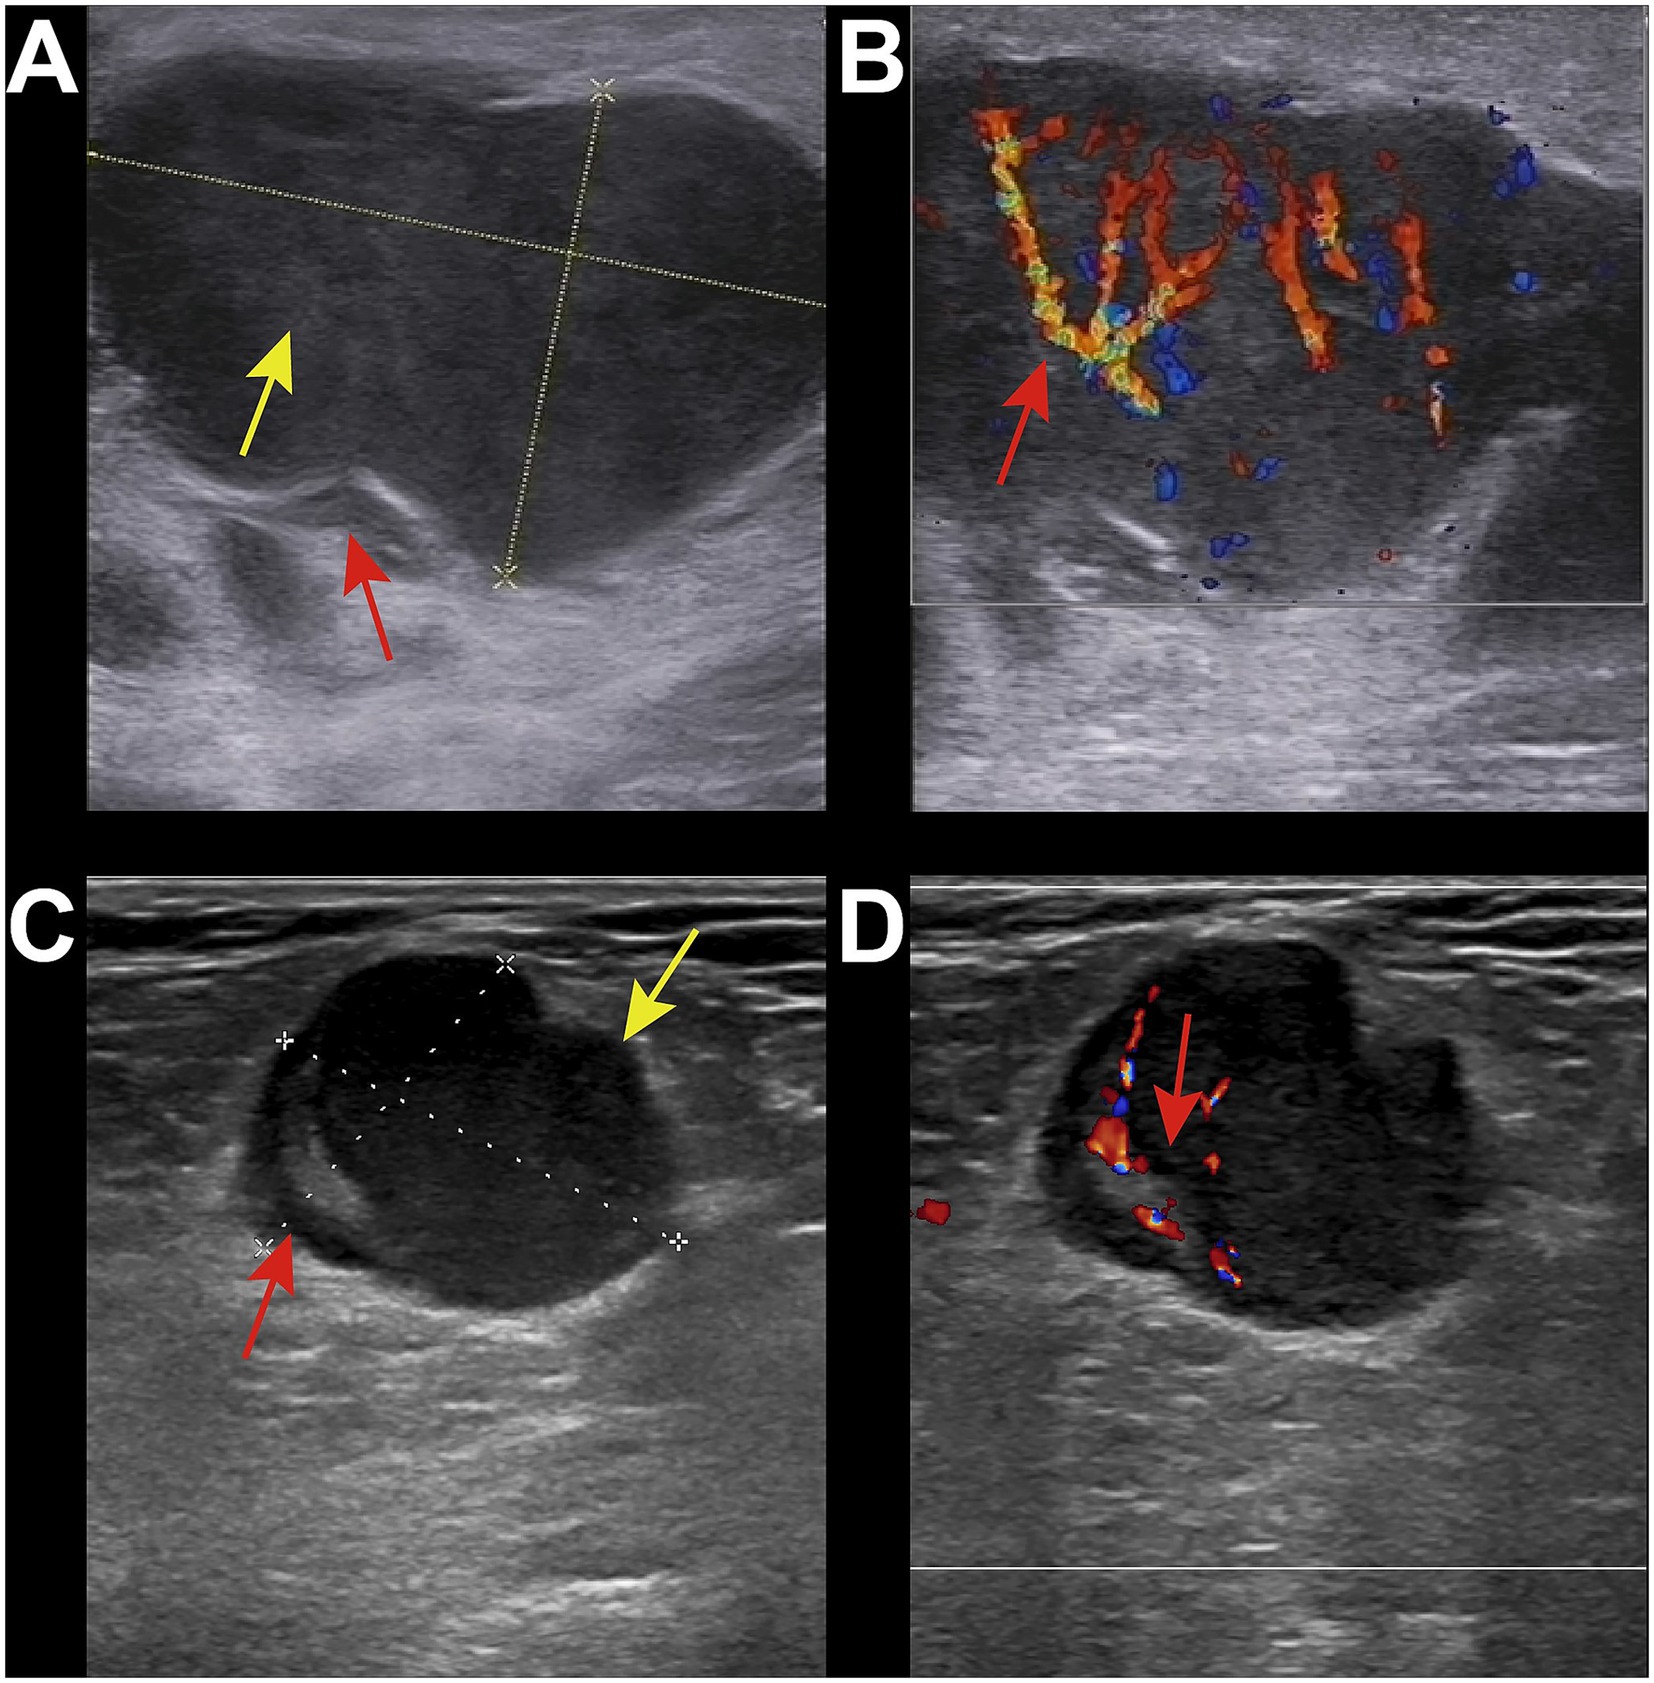

Reactive lymphadenopathy was commonly characterized by regular lymph node shape, clear margins, and the presence of a lymph node hilum, with abundant blood flow signals demonstrated on Color Doppler Flow Imaging (CDFI) (Figures 1A,B). Tuberculous lymphadenopathy varied in presentation depending on the disease stage. In the early stage, it resembled reactive lymphadenopathy. In the middle and late stages, lymph nodes fused with each other, resulting in irregular shapes and ulceration, forming sinus tracts (Figures 1C,D). Cystic changes were relatively common within the lymph nodes, and internal calcifications and surrounding soft tissue edema may be observed. Fungal infections typically presented with regular lymph node shape and mostly uniform increased echogenicity within the lymph nodes (Figures 1E,F). A few cases may showed cystic changes. The lymph node hilum was often absent or thinned. Blood flow patterns on CDFI were variable, with no significant edema in the surrounding tissues and no calcifications observed. Lymphoma involvement of lymph nodes usually manifested as round or oval lymph nodes with a full appearance, which fused (Figures 2A,B). When fused, the lymph nodes were often large, sometimes exceeding 10 cm, and the shape was usually irregular. The lymph node hilum was frequently absent. With low gain settings, the lymph node may appear anechoic, while increasing the gain reveals a reticular echogenic pattern within the lymph node. Metastatic lymph nodes were often multiple, with round or irregular shapes and an L/S ratio <2 (Figures 2C,D). The margins were clear, but may appeared blurred if the lymph node capsule was invaded. The lymph node hilum may be thinned, compressed eccentrically, or even completely absent. The cortex was irregularly thickened, and the internal echogenicity was heterogeneous.

Figure 2. Ultrasound images of malignant group. (A) 34-year-old male, diagnosed with HIV infection for 1 year. Right inguinal lymph node enlargement was with local capsule indentation and irregular shape (red arrow). The internal echogenicity showed a reticular pattern (yellow arrow), with the absence of the lymph node hilum. (B) CDFI showed abundant blood flow signals (red arrow). The pathological diagnosis was non-Hodgkin lymphoma-diffuse large B-cell lymphoma. (C) 50-year-old male, diagnosed with HIV infection for 5 years. Enlarged lymph node was in the right inguinal region with irregular shape and significant asymmetric cortical thickening (red arrow). The lymph node hilum was present but compressed and eccentric (green arrow). The internal echogenicity was relatively uniform. (D) CDFI showed abundant hilar blood flow signals (red arrow). The pathological diagnosis was metastatic squamous cell carcinoma.